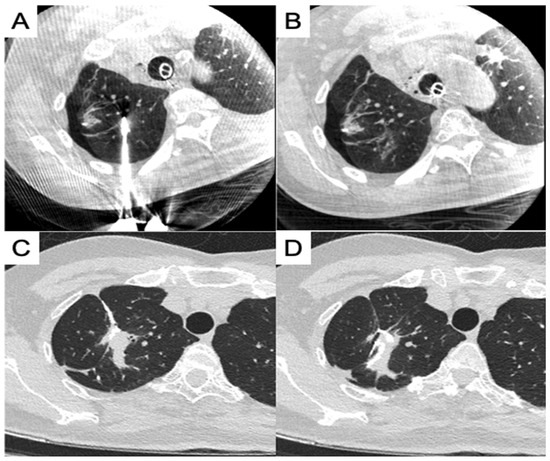

- Chan, P.S.; Chang, L.K.; Malwade, S.; Chung, W.Y.; Yang, S.M. Cone beam CT derived laser-guided percutaneous lung ablation: Minimizing needle-related complications under general anesthesia with lung separation. Acad. Radiol. 2024; in press. [Google Scholar] [CrossRef]